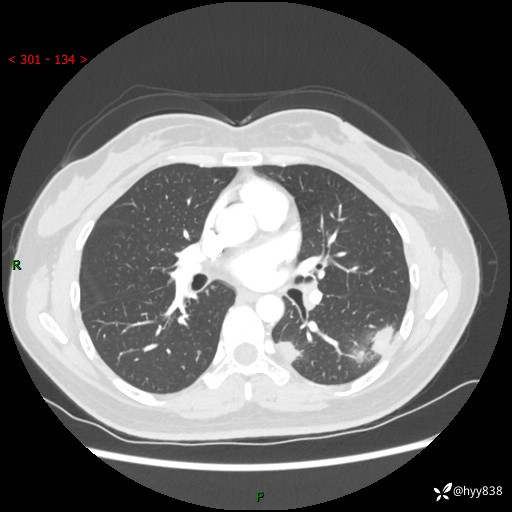

36岁/女,左侧下胸部阵发性疼痛2周,乏力1周。精彩无限,等你来诊---结果公布~

【患者信息】:36岁/女

【主诉】:左侧下胸部阵发性疼痛2周,乏力1周

【现病史及既往史】:患者自诉2周前饮酒后出现左侧下胸部阵发性疼痛,不随呼吸改变,无咳嗽咳痰、头晕头痛、咳血、呼吸困难等不适,于当地第一人民医院查胸部CT提示肺部感染,随后前往我院门诊给予抗感染(左氧氟沙星)治疗1周,自诉胸痛较前好转,感乏力、头晕,偶尔干咳,无咳痰,无发热、畏寒、胸闷、咯血、四肢酸痛、腹泻、腹痛等不适,门诊复查胸部CT提示:左肺下叶感染,病灶较前增加增大,遂以“肺部感染”收入我科。 起病以来,患者精神、饮食、睡眠可,大小便正常,体力体重无明显变化。

【检查】:胸部CT增强(外院平扫)